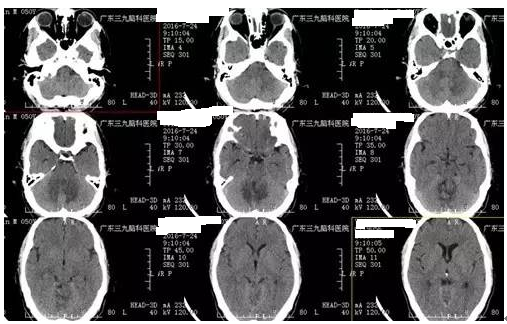

↑术前CT

间变型星形细胞瘤又称恶性星形细胞瘤,多形性星形细胞瘤,或Kernoban氏星形细胞瘤III级,是由星形细胞瘤恶变而来,其恶变发生率占14.25%。肿瘤在颅内大多数为浸润性生长,边界欠清晰,内密度不均匀,囊变多见,偶见钙化和出血,病变占位效应明显,周围可见血管源性水肿,早期扫描时病变可见不规则斑片强化,也少数为轻度强化或无强化。本例患者病变发生在小脑,CT见低密度影,内有斑片状稍高密度影,病灶中有一小囊性病变,囊变区呈低信号,稍高密度提示钙化可能,不规则强化。